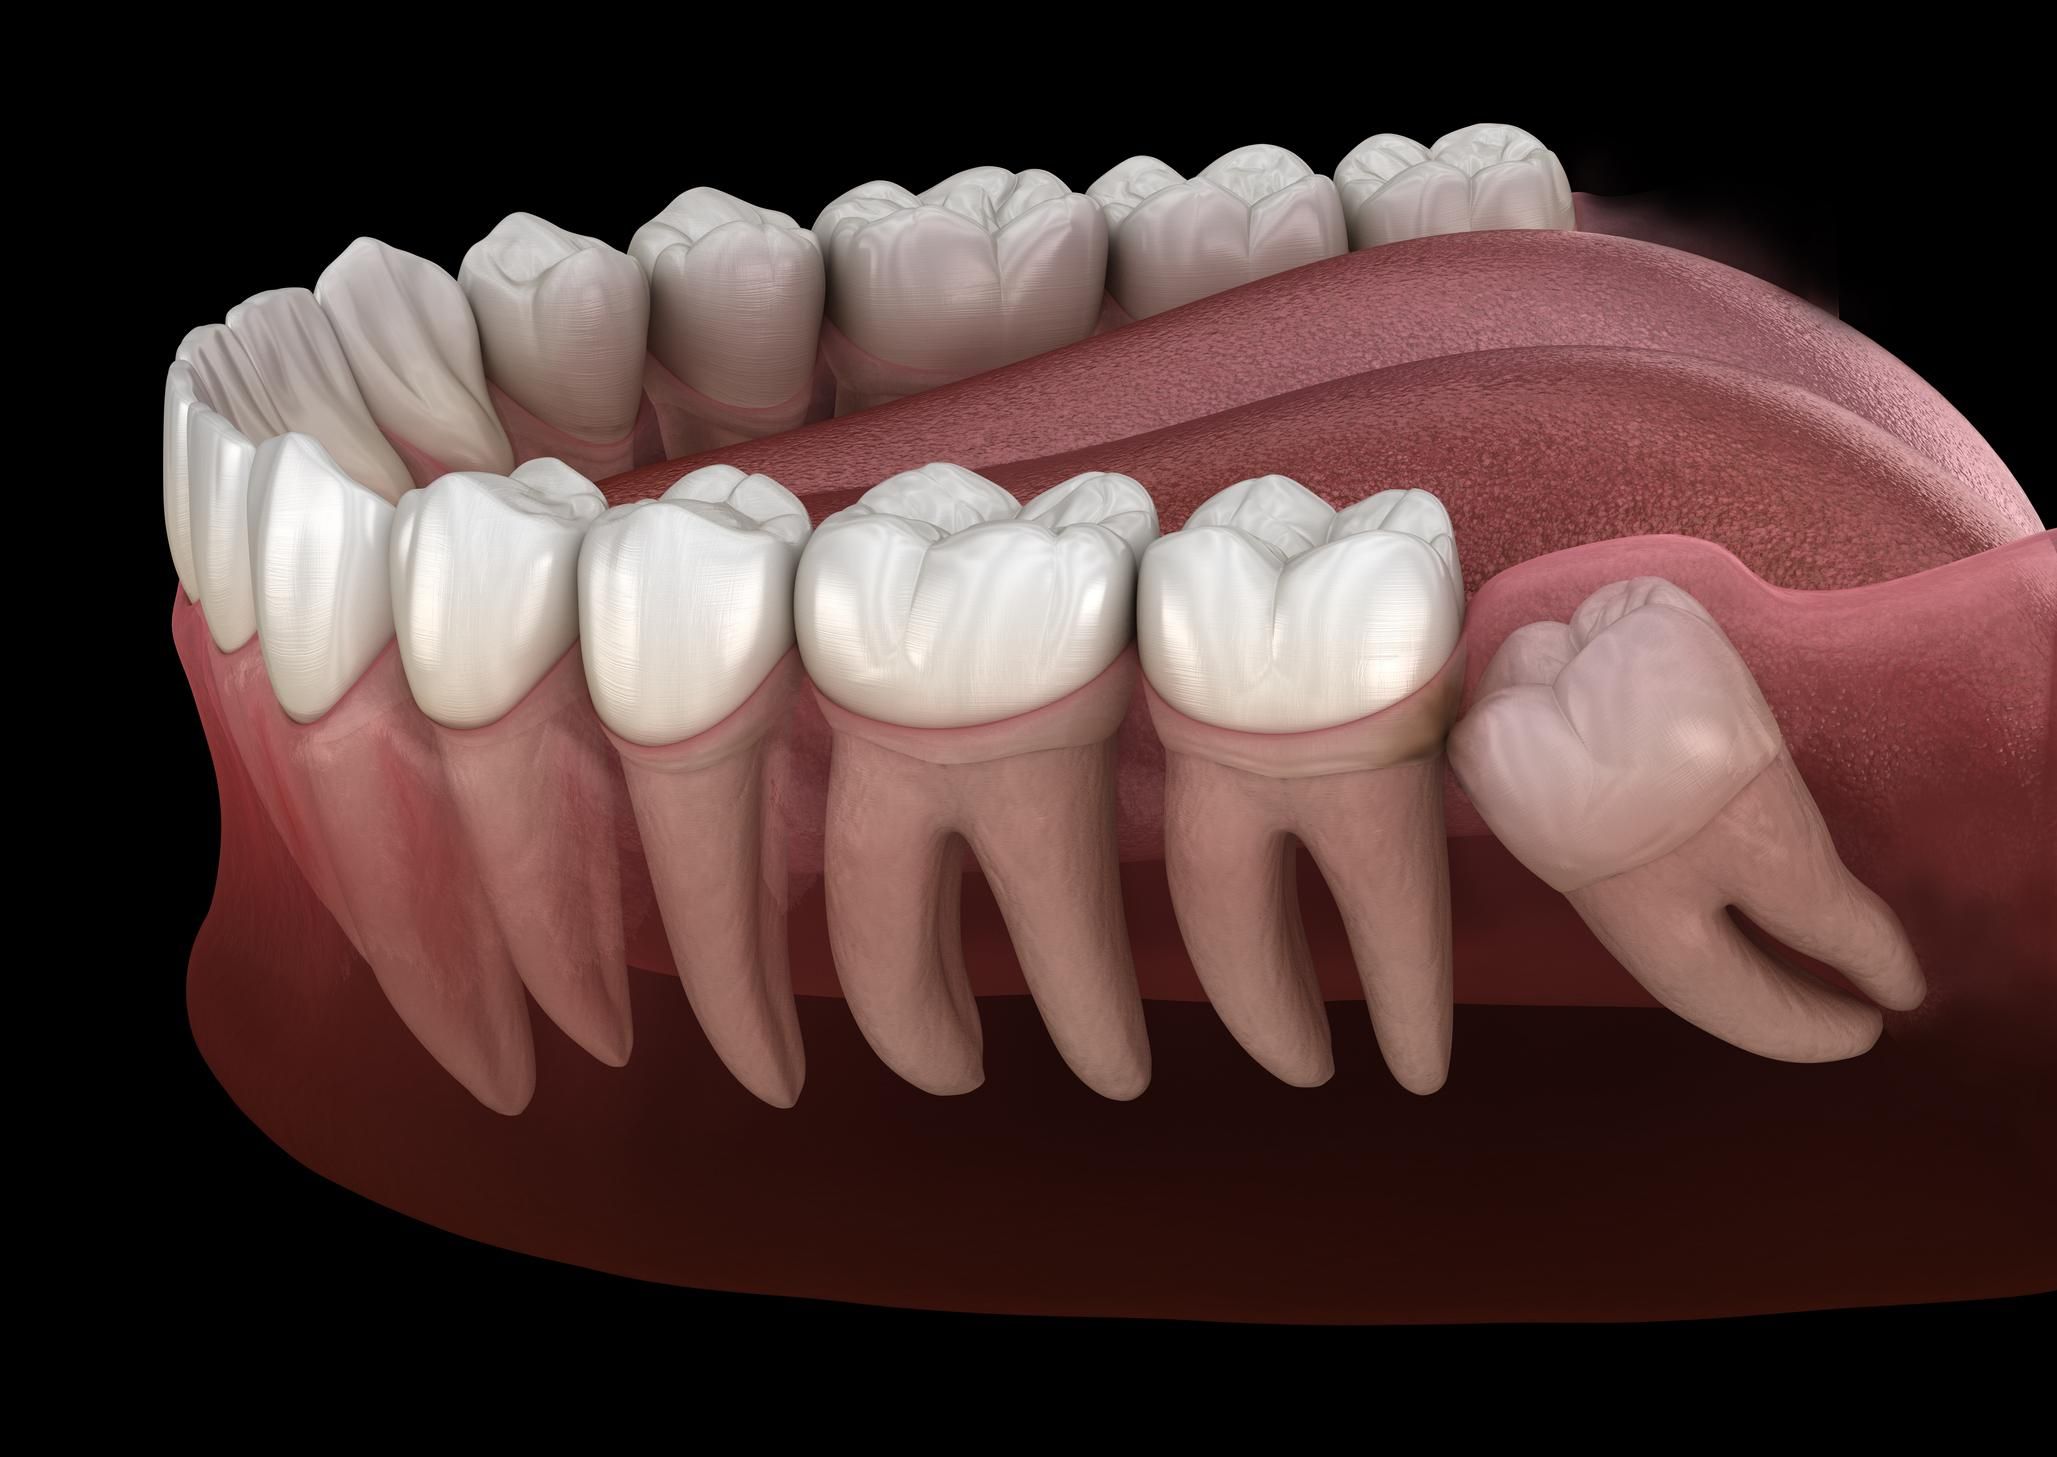

Так, більшість людей народжуються із зубами мудрості, які зазвичай прорізуються у віці 18-27 років. Ці зуби були потрібні людям у стародавні часи для пережовування сирої чи дуже твердої їжі, однак на сьогодні вони є зайвими і чимало стоматологів рекомендують їхнє видалення.

Зуби мудрості були потрібні людям у стародавні часи для пережовування сирої їжі / Фото: Getty Images

"Оскільки обличчя стає меншим, для зубів мудрості не залишається багато місця, бо щелепа зменшилась", – пояснила доктор Теган Лукас із Університету Фліндерс.